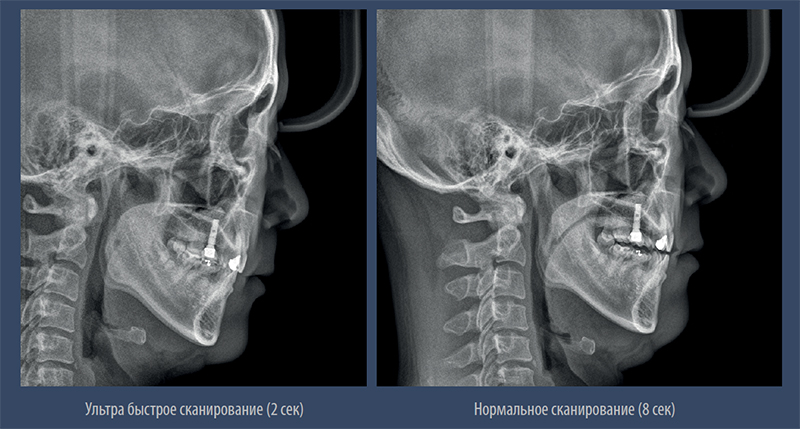

Режим быстрого сканирования.

– Минимальная доза облучения в режиме быстрого сканирования

– Качественное изображение без артефактов движения и искажений

Режим быстрого сканирования.jpg

– Быстрый режим позволяет получить качественное цефалометрическое изображение без артефактов движения и искажений